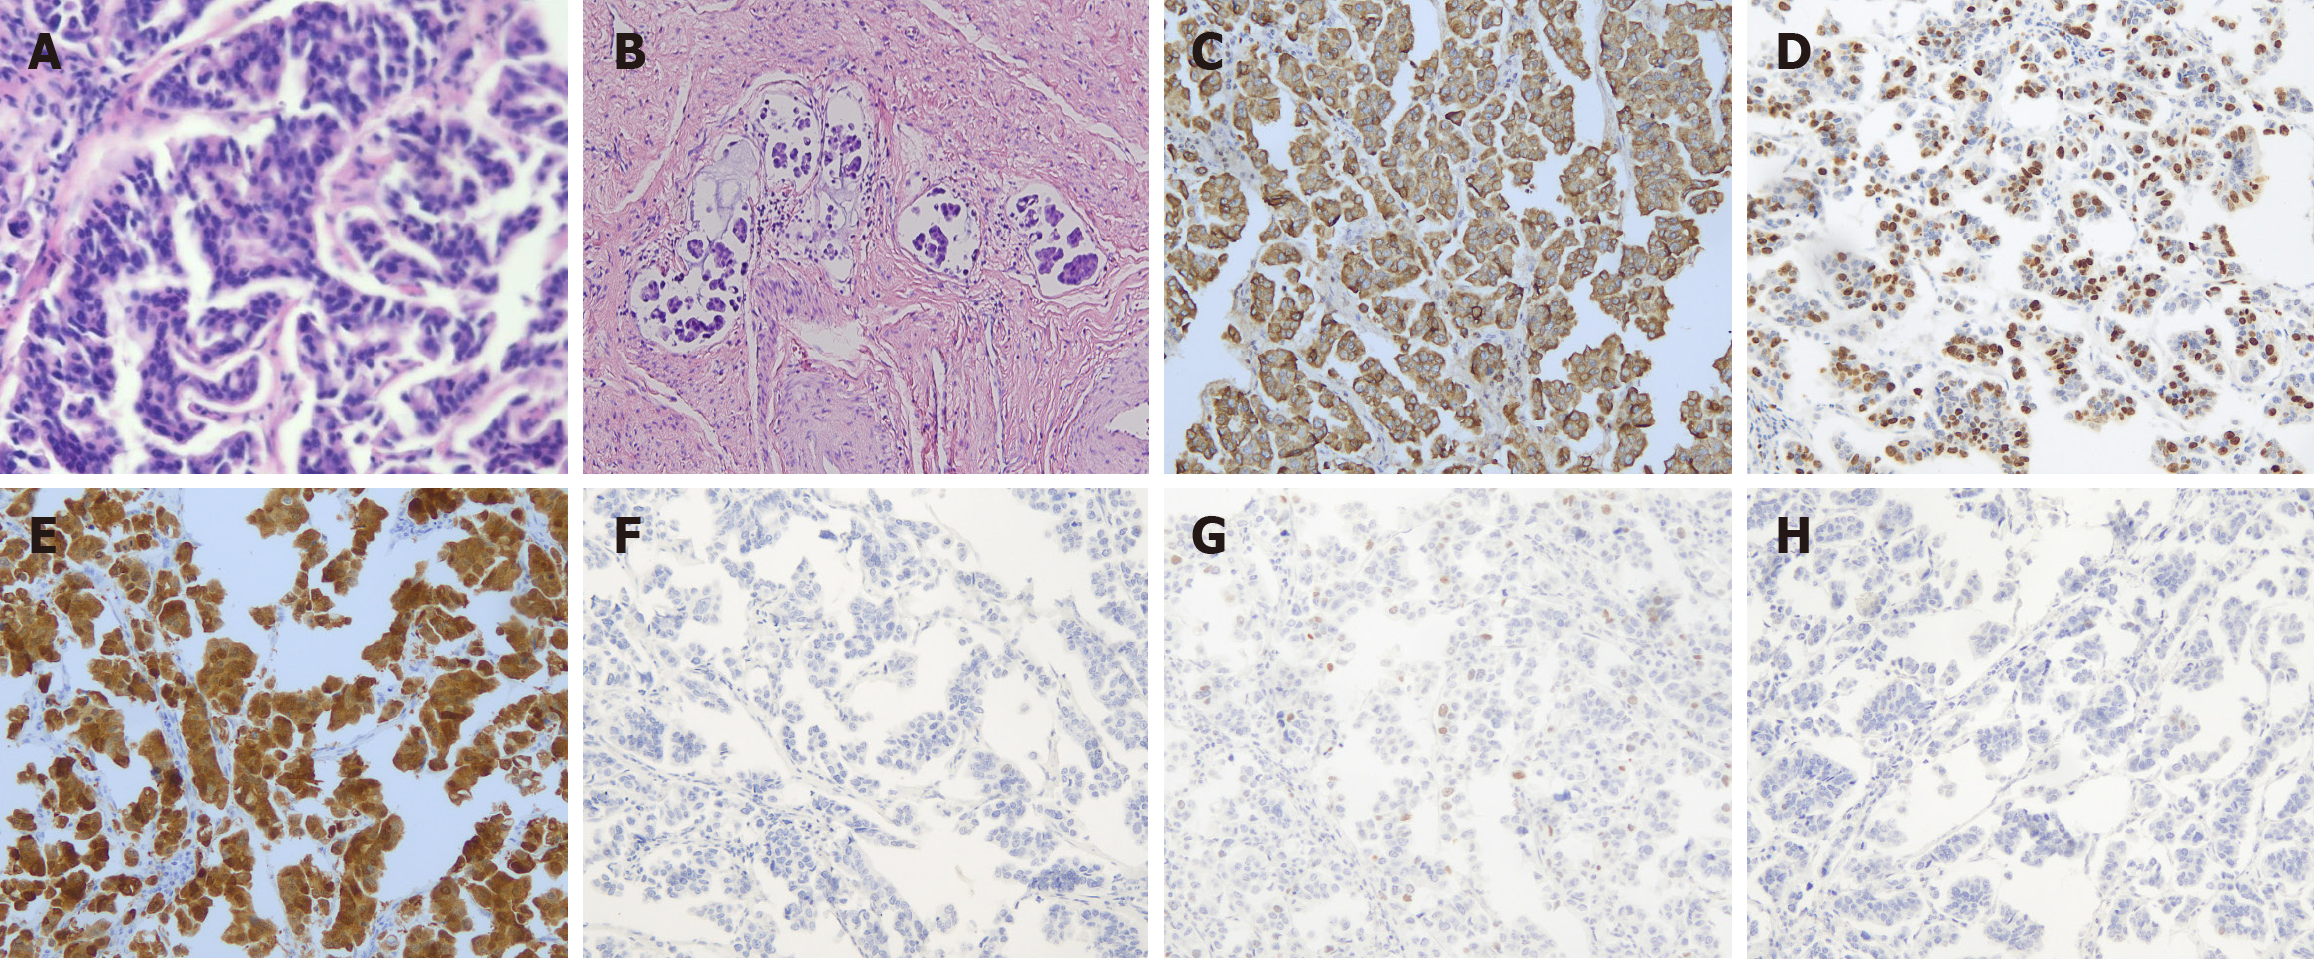

Figure 2 Cell clusters.

A: Pathological images of hematoxylin and eosin-stained samples showing high-grade serous carcinoma (H&E × 40); B: The micropapillary components form a large number of cancer emboli within the blood vessels; C: EMA; D: Ki67; E: P16 revealed diffusely positive staining (EnVision × 100); F: NapsinA; G: P5; H: WT1 all yielded negative results (EnVision × 100).